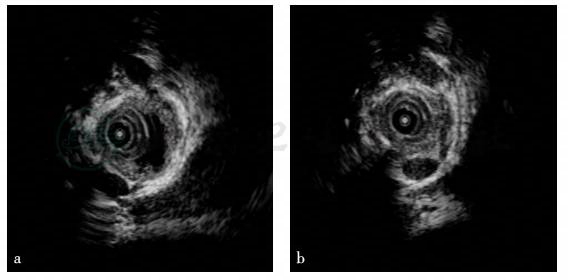

(4)胆管内超声(intraductal-ultra sonography,IDUS)

狭窄处胆管壁呈明显均匀增厚,胆管壁浆膜层完整(图5)。

图5 胆管内超声结果